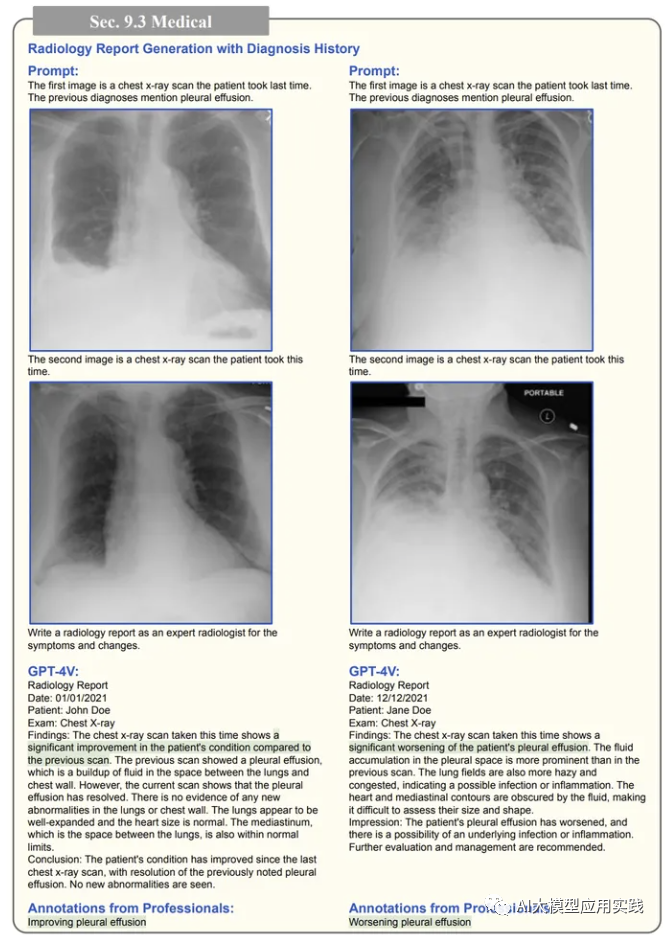

- 医疗辅助诊断

根据医学图像,生成完整的医学报告。虽然这是一个需要极大的专业知识的领域,但是可以大大减少专业人士起草报告的工作量。而且在 生成报告时,甚至可以参考先前的医学诊断历史来判断。

提供连续的医疗影像,要求AI编写医疗报告